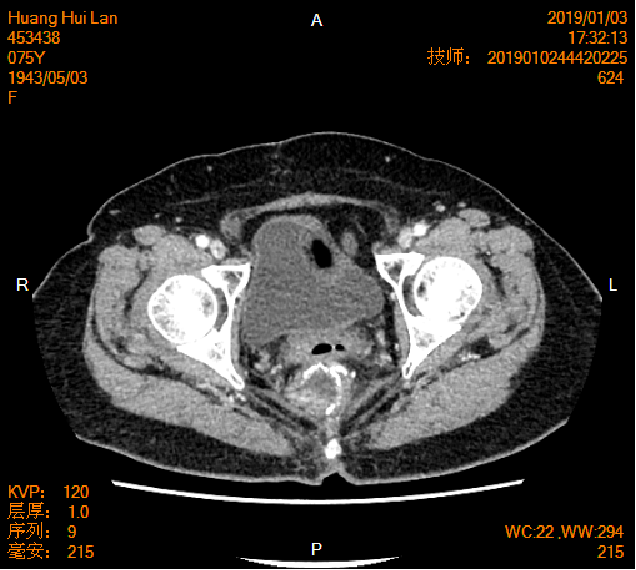

2016-04-13胸腹盆CT

2016-4-22行剖腹探查术+全子宫及双附件切除术+大网膜切除术+Dixons术(骶前保肛直肠癌根治术)

(盆腔肿物)约15X10X3cm,切面灰白,质脆,镜下:可见卵巢结构,其内见腺癌浸润。免疫组化:癌细胞CK20(+),CK(+),CDX-2(+),M-CEA(+),Villin(+),TTF-1(-),CK7(-)。符合直肠腺癌卵巢转移。

直肠中分化腺癌双肺卵巢转移 RAS突变 pT4aN1aM1b

2019-01-04胸腹盆CT